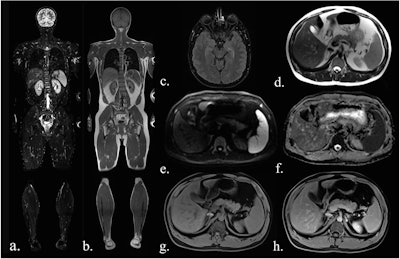

Sequences included in the study MRI protocol: (a) coronal TIRM (turbo inversion recovery magnitude) sequence, (b) coronal T1-weighted sequence, (c) axial FLAIR (fluid-attenuated inversion recovery) sequence (head only), (d) axial T2-weighted fast spin-echo sequence (HASTE), (e) axial diffusion-weighted imaging (b-value 900), (f) an axial ADC map, (g) axial T1-Dixon water-only images before contrast agent, and (h) after administration of contrast agent.All figures courtesy of Dr. Myriam Keymling et al and European Radiology

Sequences included in the study MRI protocol: (a) coronal TIRM (turbo inversion recovery magnitude) sequence, (b) coronal T1-weighted sequence, (c) axial FLAIR (fluid-attenuated inversion recovery) sequence (head only), (d) axial T2-weighted fast spin-echo sequence (HASTE), (e) axial diffusion-weighted imaging (b-value 900), (f) an axial ADC map, (g) axial T1-Dixon water-only images before contrast agent, and (h) after administration of contrast agent.All figures courtesy of Dr. Myriam Keymling et al and European Radiology

Combinations of sequences were assessed in order to determine the optimal protocols. The analysis included turbo-spin echo (TSE) T1-weighted and inversion-recovery T2-weighted (TIRM) images of the whole body in coronal orientation, and T2-weighted (HASTE), diffusion-weighted (DWI), and T1-weighted DIXON images (pre- and postcontrast agent administration) from head to thighs in axial orientation. An additional fluid-attenuated inversion recovery (FLAIR) sequence was used for the skull only.

FLAIR and DWI sequences, alone and in combination, demonstrated the best results for all lesions (benign, ambiguous, malignant). DWI achieved the highest score for imaging malignant lesions in the entire body (86% of lesions categorized as “easily detectable”), while FLAIR had the best results for lesions of the head (100% of “easily detectable” lesions). DWI and FLAIR consistently demonstrated the highest ratings for malignant lesions of two-sequence combinations. The most effective three-sequence combination for all lesions was DWI and contrast-enhanced T1W with TIRM, according to the findings.